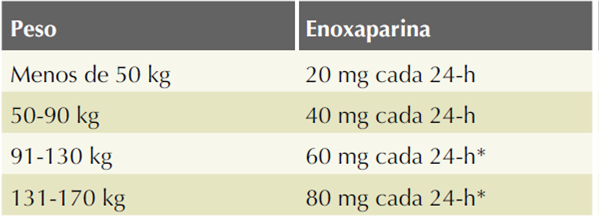

El tratamiento de pacientes con trombosis venosa cerebral consta de medidas generales y prescripción de medicamentos. Como medidas generales, se considera la posición de la cabecera a 40 grados y oxigenación adecuada (dependerá del estado de conciencia y afectación de la vía aérea).9

El tratamiento anticoagulante, en casos de trombosis venosa cerebral en el embarazo y puerperio, es seguro y se asocia con reducción potencial del riesgo de muerte o dependencia.3 La indicación de estos se basa en la reversión del proceso trombótico y como prevención de complicaciones tromboembólicas agregadas en otros sitios anatómicos. Los anticoagulantes no tienen efecto trombolítico, por lo que su indicación se limita a prevenir el crecimiento del trombo. Los anticoagulantes durante el embarazo y el puerperio incluyen: heparinas no fraccionadas, heparinas de bajo peso molecular (HBPM) y warfarina. Los anticoagulantes preferidos para prescripción durante el embarazo son los compuestos de heparina porque no cruzan la barrera hemato-placentaria.10 De estos, las heparinas de bajo peso molecular se consideran mejores que las heparinas no fraccionadas, porque se les vincula con menos episodios de hemorragia, respuesta terapéutica más predecible, menor riesgo de trombocitopenia, mayor vida media y menor pérdida de densidad ósea.10 Se recomienda la prescripción de algún compuesto de heparina (por lo general, una heparina de bajo peso molecular porque no requiere ajuste de dosis-respuesta) y continuar con un anticoagulante oral. La enoxaparina, un tipo de heparina de bajo peso molecular, es un profiláctico que se indica a una dosis de 40 mg/día, por vía subcutánea. En dosis terapéuticas, 1 mg/kg cada 8 horas. Sin embargo, la dosis profiláctica debe ajustarse al peso de la paciente. (Cuadro 5) Los anticoagulantes orales, los antagonistas de la vitamina K, como la acenocumarina, aunque están contraindicados durante el embarazo, pueden prescribirse en el puerperio por al menos seis semanas y suspenderlos a los tres meses posparto, aunque el tratamiento puede mantenerse hasta por seis meses. Para el monitoreo de la acenocumarina, el INR debe mantenerse entre 2.0-3.0.11

Cuadro 5 Dosis profilácticas de enoxaparina durante el embarazo y puerperio

Puede administrarse en dos dosis.

Fuente: Royal College of Obstetricians and Gynaecologists. Reducing the Riskof of Venous Thromboembolism During Pregnancy and the Puerperium: Acute Management. Green-top Guideline No. 37a. London: RCOG; 2015.9